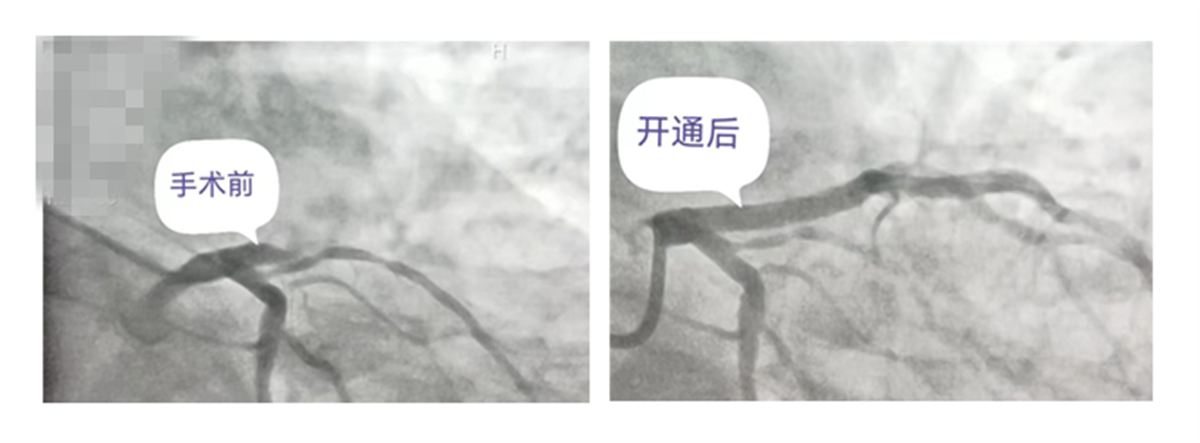

爭分奪秒,無縫對接。趙先生以最快的速度被送到晉城大醫(yī)院,等候多時的心血管內(nèi)科、急診醫(yī)學(xué)科立即為患者做急診冠狀動脈造影檢查,提示前降支開口閉塞。焦延景副主任以最快的速度找到病變血管,開展心臟介入治療。

導(dǎo)絲順利通過閉塞病變,但是發(fā)現(xiàn)血栓負荷很重,緊急進行了冠脈內(nèi)血栓抽吸以及球囊擴張?zhí)幚怼?br/>

“病人突發(fā)室顫,馬上進行電除顫!”焦主任沉著冷靜,發(fā)布指令。電除顫后,心律恢復(fù)為竇性心律。醫(yī)護人員默契配合,順利置入支架,手術(shù)結(jié)束,為患者開通生命血管,打開生命之門。

急性心肌梗死患者最好在發(fā)病開始的黃金120分鐘內(nèi)進行救治,胸痛中心要求從患者到達醫(yī)院門口到導(dǎo)絲通過的時間為90分鐘,時間越長,壞死的心肌就越多,趙先生的救治用時僅48分鐘。(圖/文 心血管內(nèi)科 焦延景)